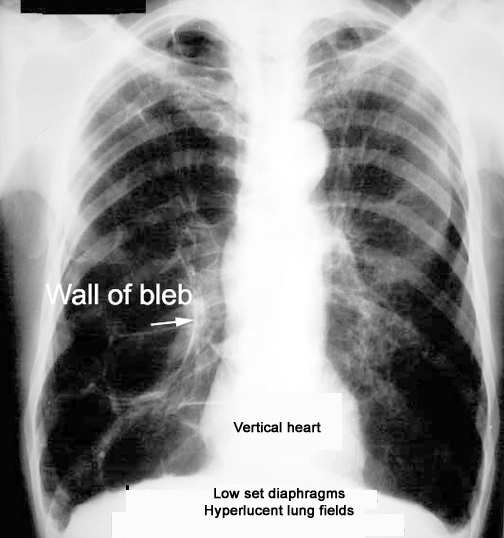

COPD CXR findings

hyperinflation, flattened diaphragm, incr retrosternal space

Decr vasculature and bullae in pts with emphysema bc alveoli are being destroyed)